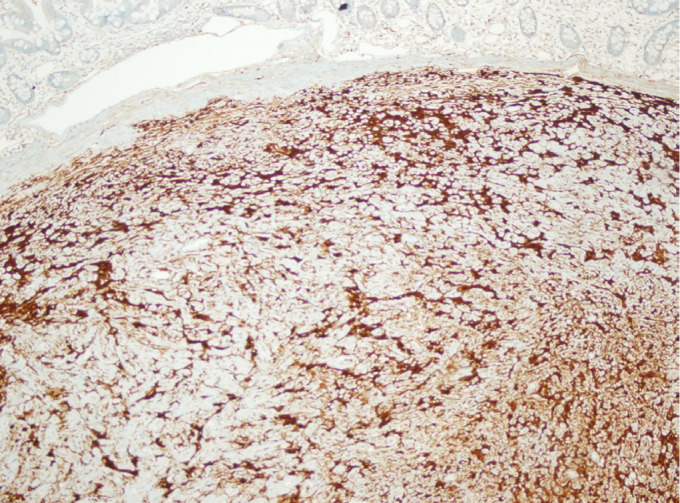

Gastrointestinal schwannomas are benign, slow-growing, rare tumors comprising 2-6% of all mesenchymal tumors of the gastrointestinal tract and 0.2% of all gastric neoplasms. In the gastrointestinal system, schwannomas are mostly observed in the stomach, followed by the colon and rectum. In this case series, we present the clinicopathological results of 9 cases, along with a literature review. A retrospective analysis was conducted on nine patients diagnosed with gastrointestinal schwannoma in a single institution. Tumors were located in the small intestine and stomach, with an average tumor size of 4.6 cm (range: 1.8-8.5 cm). Diagnoses were incidental in most cases, with only four patients presenting symptoms such as epigastric pain and changes in bowel habits. Histopathological characteristics of tumors were studied. Surgical resection with negative margins was performed in 8 cases. Histopathological analysis confirmed schwannomas characterized by solid, homogeneous, spindle-cell structures without cystic changes or necrosis. Immunohistochemically, all tumors were S-100 positive, with variable expression of other markers. Desmin was negative in seven samples. One gastric schwannoma showed focal smooth muscle actin positivity, while others were negative. The Ki-67 index ranged from 0% to 6%, and c-Kit was negative in all cases. DOG-1 expression was examined in four cases, showing focal positivity in small bowel schwannoma and negativity in three gastric schwannomas. Gastrointestinal schwannomas are predominantly benign tumors, more common in women, and typically occur in the sixth decade of life. While imaging and endoscopic techniques help in diagnosis, definitive diagnosis relies on histopathological analysis. Surgical resection remains the gold standard for treatment.